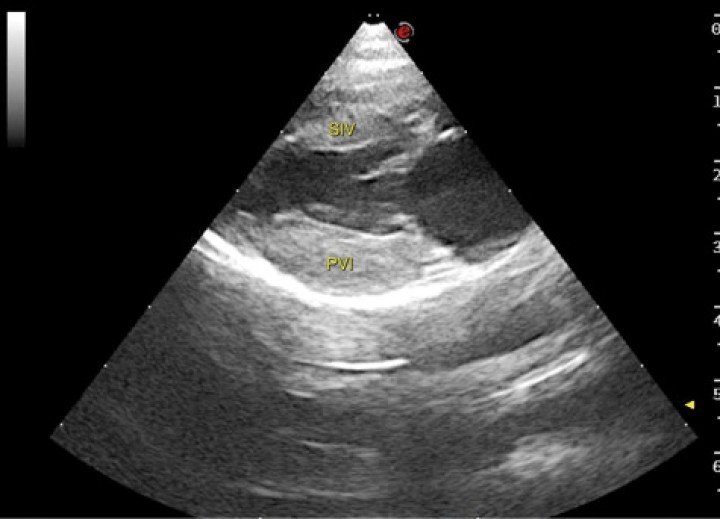

<p>Imagen ecocardiográfica paraesternal derecha en eje largo cuatro cámaras de un gato con cardiomiopatía hipertrófica. En la imagen se observa engrosamiento de la pared libre del ventrículo izquierdo (PVI) (0,81 cm) y del septo interventricular (SIV) (0,73 cm). Valores > 0,6 cm son sugestivos de CMH.</p>

Figura 5

Imagen ecocardiográfica paraesternal derecha en eje largo cuatro cámaras de un gato con cardiomiopatía hipertrófica. En la imagen se observa engrosamiento de la pared libre del ventrículo izquierdo (PVI) (0,81 cm) y del septo interventricular (SIV) (0,73 cm). Valores > 0,6 cm son sugestivos de CMH.